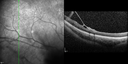

This pleasant 8-year-old child was seen in the office on March 8, 2012. He was examined for glasses and dilated examination showed retinal abnormalities.

VISUAL ACUITY: OD 20/40, OS 20/50. IOP: 12 OU. His lenses are clear.

OD: Vertical C/D ratio is 0.2. There are foveal cysts. There is also a retinal elevation inferiorly and there are patchy peripheral retinal hemorrhages.

OS: Vertical C/D ratio is 0.2. There are foveal cysts. There is peripheral retinal issues with some hemorrhage in some areas of peripheral retinoschisis.

SPECTRALIS-SD-OCT SCAN: The OCT scan does show foveal retinoschisis in both eyes. The average thickness of the macula in the right eye being 420 microns and the cysts appear to be forming predominately in the inner nuclear and inner plexiform layer. In the left eye the OCT scan shows an average central foveal thickness of 414 microns and the cysts in that eye are forming mostly in the inner plexiform inner nuclear layer. The peripheral line scans also show peripheral retinoschisis in both eyes outside the macula. It is a little bit closer in the right eye where the hemorrhage is and you can see vitreoretinal traction at the edge of the schisis cavity. (NOTE: Retinal thickness measured with Spectralis OCT is approximately 70 μm greater than that measured with Stratus OCT. This increased measurement corresponds to the inclusion of the outer segment-RPE-Bruch's membrane complex by Spectralis OCT.)